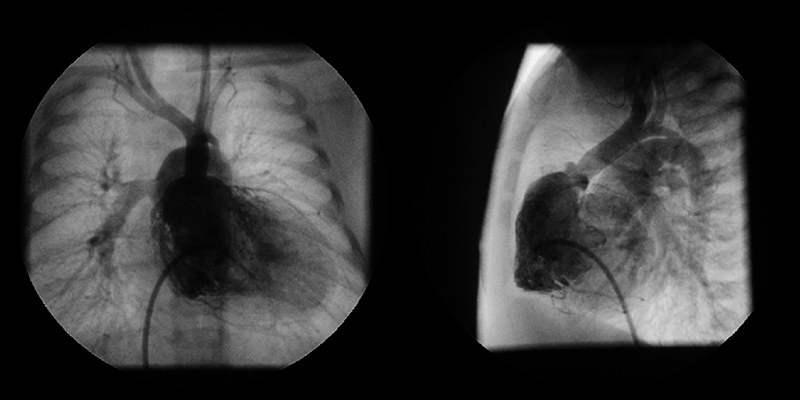

A 0-day-old boy was transferred to our hospital because of cyanosis and a heart murmur. On arrival, two-dimensional echocardiography revealed TGA, VSD, coarctation of the aorta, and a moderately hypoplastic RV with tripartite portion and a TV diameter of 7.5 mm; Z-score (the distance of the raw score value from the mean in terms of standard deviation) being −1.62. Anatomy of the coronary artery was of a usual pattern (the left anterior descending branch and the circumflex artery arising from sinus 1 and the right coronary artery from sinus 2). VSD was of a perimembranous type. RV angiography on Day 2 is shown in Fig. 1. The aortic valve diameter was 6.7 mm (Z-score: 0.14) without subaortic stenosis. Infusion of prostaglandin E1 (PGE1) was immediately initiated, but the patient developed circulatory failure due to obstruction across the ductus arteriosus. At 5 days of age, urgent bilateral pulmonary artery (PA) banding was performed; the patient was then stabilized on continuous PGE1 infusion.

Fig. 1 Right ventriculography on Day 2

Right ventricle is tripartite without obvious sub-aortic stenosis.